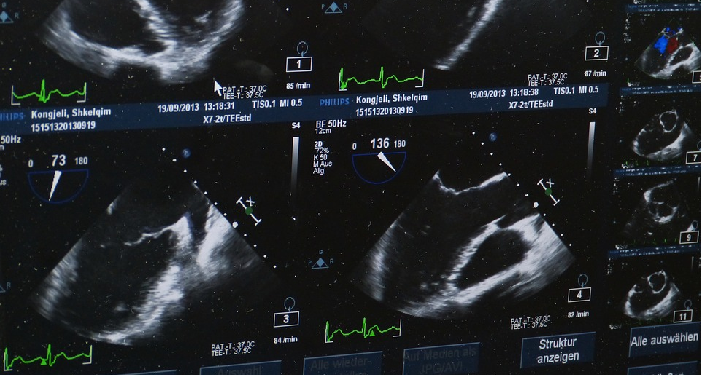

Manfaat Melakukan USG Pada Ibu Hamil

Oleh karena itu, USG ada baiknya dilakukan per trimester, karena pertumbuhan bayi pada tiap trimesternya cukup signifikan. Berikut manfaat melakukan USG per trimester menurut theasianparent.id:

Trimester pertama:

- Mengonfirmasi kehamilan.

- Memeriksa detak jantung janin.

- Menentukan usia kehamilan.

- Perkiraan tanggal lahir bayi (HPL).

- Memeriksa kemungkinan kehamilan kembar, kondisi plasenta, uterus, ovarium dan serviks.

- Mendiagnosis kehamilan ektopik.

- Melihat abnormalitas janin.

Trimester ke dua:

- Mengetahui jenis kelamin bayi.

- Memantau pertumbuhan janin dan kelengkapan organ vital (jantung, paru-paru, otak).

- Mengonfirmasi kehamilan kembar.

- Memeriksa masalah abnormalitas plasenta.

- Mengetahui kelainan struktural.

- Memantau cairan ketuban.

- Memeriksa masalah sirkulasi darah.

- Mengetahui kadar oksigen pada janin.

- Mendiagnosis masalah pada rahim.

Trimester ke tiga:

- Memprediksi hari kelahiran.

- Mengetahui posisi janin.

- Memeriksa fungsi plasenta.

- Memeriksa kelainan bawaan atau cacat lahir.

Pentingnya Bunda mengetahui keadaan janin secara berkala, agar bisa melakukan pencegahan jika janin membutuhkan perawatan khusus.

Seberapa seringnya pemeriksaan USG dilakukan bergantung pada kondisi kehamilan Bunda. Jika termasuk yang berisiko tinggi, maka pemeriksaan USG bulanan akan lebih sering dilakukan. [Ln]